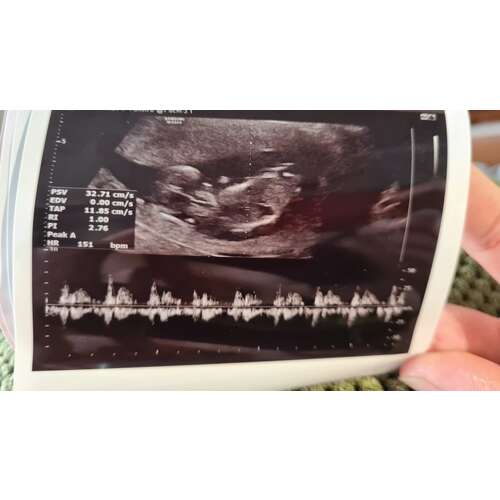

Vandaag controle gehad. Ben 12+1 Iemand idee welk t wordt? Snap niet veel van die nub theorie :p Vandaag nipt gehad dus volgende week weet ik wrs het geslacht wel

Vandaag controle gehad. Ben 12+1 Iemand idee welk t wordt? Snap niet veel v ...

Het beentje zit ervoor. Waardoor ik de nub niet kan zien. Had je niet meer echo's?

Dit is de andere foto

Aan 1 kant lijkt het een meisjes nub. Maar door het kleine streepje bolletje boven de nub (is duidelijker te zien na het verscherpen van de foto) lijkt het een jongetjes nub aan het worden. Sommige jongetjes laten zich iets later pas duidelijk zien. En denk dus dat dat bij dit kleintje het geval is. Dus ik gok jongetje ( maar niet heel zeker)